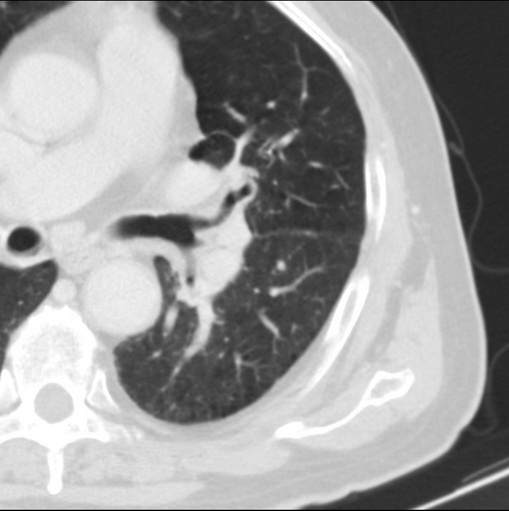

男性患者 81岁 咳嗽 咳痰 咯血

左肺中心型肺癌并:1.左肺阻塞性肺炎;2.纵隔淋巴结肿大;

考虑左上肺癌并阻塞性肺炎,左肺转移、左肺门及纵隔淋巴结转移。

肿块贴近左肺门,包绕左上肺动脉,形态不规则。肿块增强扫描中度强化。纵膈内主动脉弓左旁间隙、气管隆突前、下间隙见多枚淋巴结影。综上考虑左侧中央型肺癌可能性大。图片没有完整上传,尤其是左肺上叶支气管分支层面没有上传,因此不好判断是叶支气管中断还是段支气管中断。另外,下图红色部分所示是“黏液支气管征”吗?